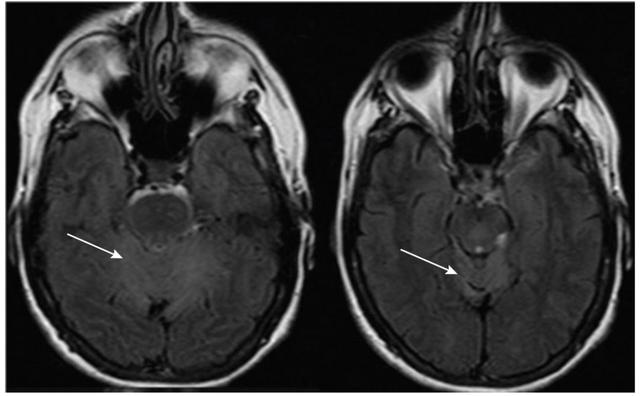

引起急性共济失调的其他疾病包括莱姆病,Whipple病,曲霉菌病,JC病毒,梅毒和克雅病等。亚急性共济失调和脑MRI异常(图1)可能是由JC病毒感染引起的。

图1 表现为亚急性小脑性共济失调的HIV患者。脑脊液PCR证实John Cunningham病毒感染(进行性多灶性白质脑病小脑型);A-B:T2WI和FLAIR可见小脑不对称高信号,累及左侧小脑半球和小脑中脚。